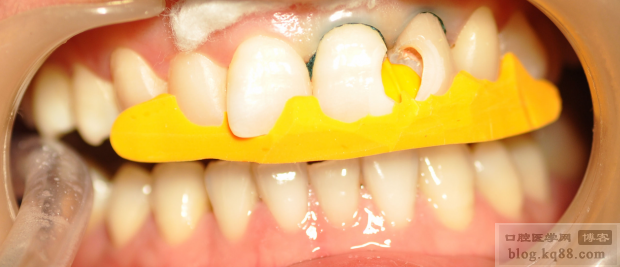

分層充填,其中背板我用的是GC的幻彩樹脂,中間用的KERR的樹脂

下面是充填完成還未進行調(diào)磨的照片

調(diào)磨拋光后,21的顏色稍微還有一點色差,自己不是很滿意,但是患者已經(jīng)很滿意